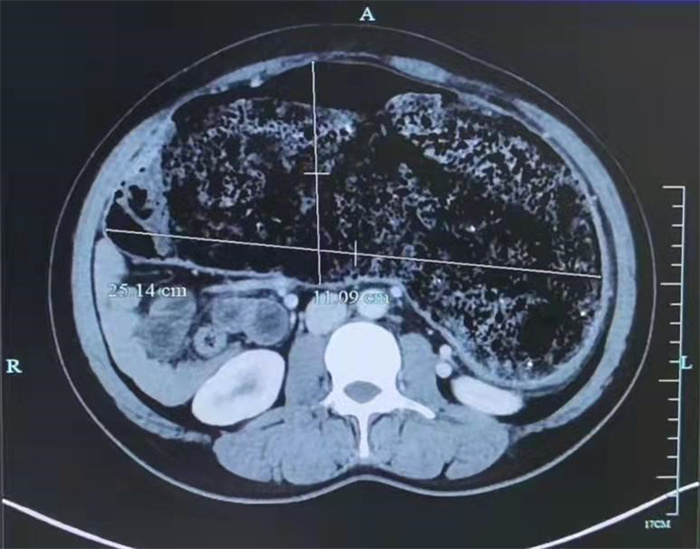

詳細(xì)詢問(wèn)病史結(jié)合全腹部CT增強(qiáng)檢查,提示何女士乙狀結(jié)腸、降結(jié)腸管腔明顯擴(kuò)大(較寬處管徑約25.14cm),考慮先天性巨結(jié)腸。為徹底解除何女士的困擾,徐天生建議何女士手術(shù)治療。

歷經(jīng)4小時(shí),何女士順利接受了腹腔鏡下全結(jié)腸切除術(shù),取出的結(jié)腸足足比胃還大。